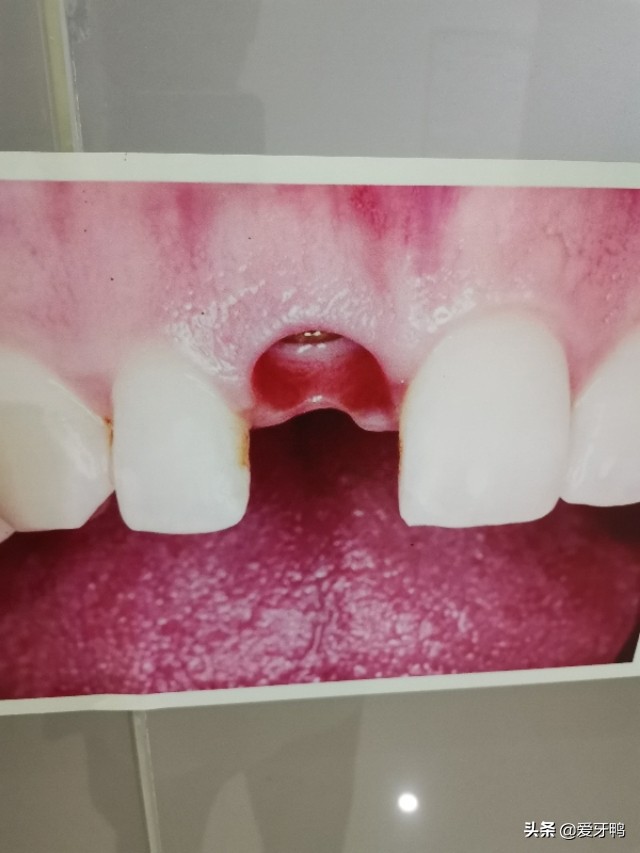

牙齿周围的一圈,有一种0.15~0.38mm的组织叫牙周膜,牙周膜中有大量的胶原纤维将牙齿固定在牙槽窝内。而且牙周膜中有成牙骨质细胞、成骨细胞、未分化细胞,这些细胞有一定再生能力。因此掉出来的牙齿再放回去是可能重新“长稳”的(牙再植),所以小孩如果牙齿磕掉了,首先把牙齿找回来!

遵医嘱!就是“听医生话”。牙再植会出现牙根吸收、牙髓坏死等、牙内吸收等并发症。牙再植后4周、3、6、12个月要进行复查,若发现有牙髓坏死等并发症要进行相关治疗,不要以为“感觉牙已经长好了”就万事大吉!